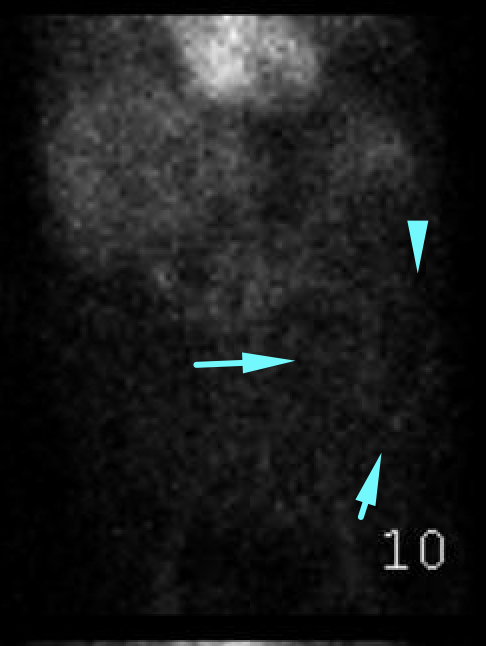

Age: 69

Sex: Male

Indication: GI bleeding

Radiotracer: Tc99m labeled RBCs

Sample ReportNo evidence of active GI bleeding during the course of this study.